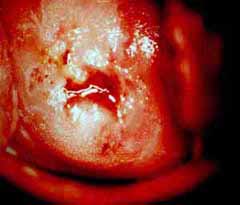

Κολποσκοπικές εικονες για τις αναγκες του forum.